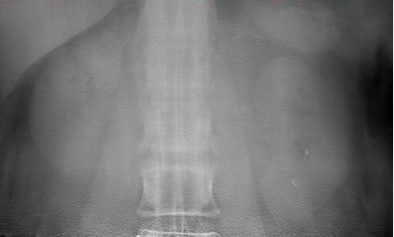

![]() |

| Two lithiasis in left kidney, seen on both techniques but much clearer on the tomosynthesis image (above), as well as nice visualization of the contour of the kidney. Images courtesy of Dr. Koen Mermuys. |